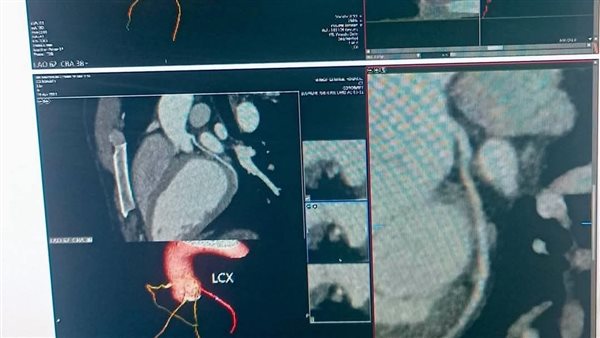

نقلة طبية جديدة بمستشفى منوف العام.. تنفيذ أول أشعة مقطعية متطورة لشرايين القلب بدون جراحة

في إنجاز طبي متميز، أعلنت مستشفى منوف العام عن نجاحها في إجراء أول أشعة مقطعية متعددة المقاطع لشرايين القلب، وذلك للكشف المبكر عن ضيق وانسداد الشرايين التاجية بدون الحاجة لأي تدخل جراحي، ما يعد خطوة رائدة تعزز جودة الرعاية الصحية داخل محافظة المنوفية.

وتسهم هذه الخدمة الطبية الجديدة في الكشف الدقيق عن أمراض القلب بشكل مبكر، ما يعزز فرص الوقاية والتدخل السريع للعلاج، ويقلل من المضاعفات الخطيرة التي قد تهدد حياة المرضى، خاصة مع الاعتماد على أجهزة أشعة مقطعية تعد الأحدث على مستوى العالم.